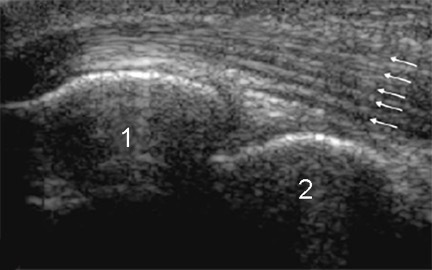

Posterior Elbow Anatomy Image

Olecranon Process

Trochlea of the Humerus

Arrows: Triceps Tendon